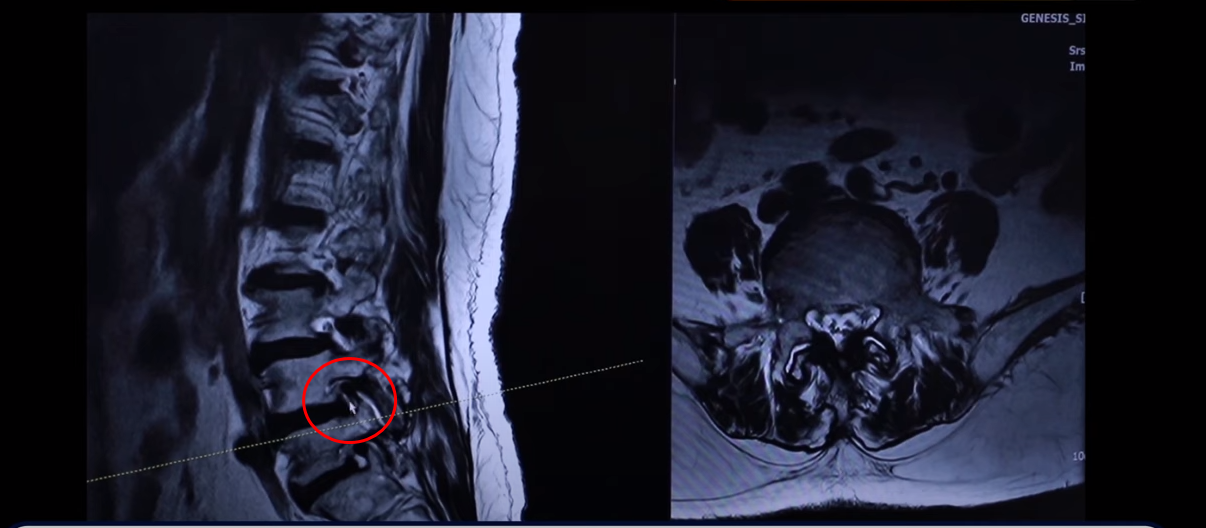

그런데 특히 이 아랫마디 가보면 여기가 많이 좁아져 있습니다. 특히 뭐가 문제냐면 이 척추관보다는 여기 추간공을 보면 이렇게 좁아져 있습니다. 다른 데하고 굉장히 크게 차이가 많이 나죠.

이제 이렇게 환자들이 이런 걸 보시면 아예 까맣게 변해 있다. 신경이 많이 눌리니까 이게 왼쪽 다리로 가는 신경입니다. 그 다음에 오른쪽 다리로 가는 신경을 보면 신경이 여기 지금 까맣게 보입니다. 이 지방이 다 없어져버린 겁니다. 신경 공간이 좁아져 있죠.

그 다음에 이거는 디스크고 이 뒤에 있는 건 황색인대입니다. 이것들이 지금 두꺼워져 있기 때문에 여기 공간이 좁아지는 겁니다. 그래서 이제 오른쪽 다리, 왼쪽 다리가 다 신경이 눌리고 아파서 못 걷는 분입니다.

그러면 이런 분들은 뭐라고 얘기를 듣냐면 수술을 하는데 여러 마디가 안 좋다 보니, 가령 이 마디는 전방 전위가 있고 이 마디는 심하게 양쪽 다리로 가는 양쪽 신경 구멍들이 좁아져 있는 거죠. 그러면 여러 마디 수술을 해야 되는데 또 전방전위도 있기 때문에 나사를 박는 수술을 해야 된다고 듣는 경우가 많습니다.